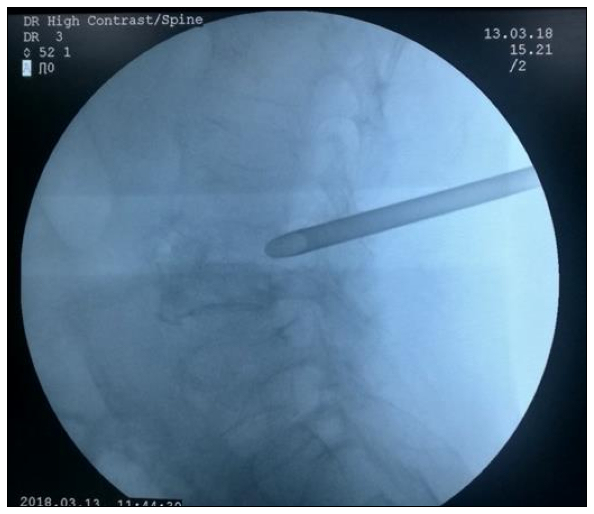

经充分术前准备后,于2018年3月13号下午,由袁中山主任和他的团队实施微创椎间孔镜手术治疗,手术在局麻下顺利完成,历时2小时左右,手术切口8mm,手术出血仅约10ml,术后病人腰腿痛明显好转,翻身不痛了,咳嗽也敢咳了,也能下床走路了,患者又露出开心的笑容。术后患者高兴的说:“感谢你们用这样一种神奇的方法解除了我的病痛,你们本身真大!”。患者已于2018年3月28日顺利出院。